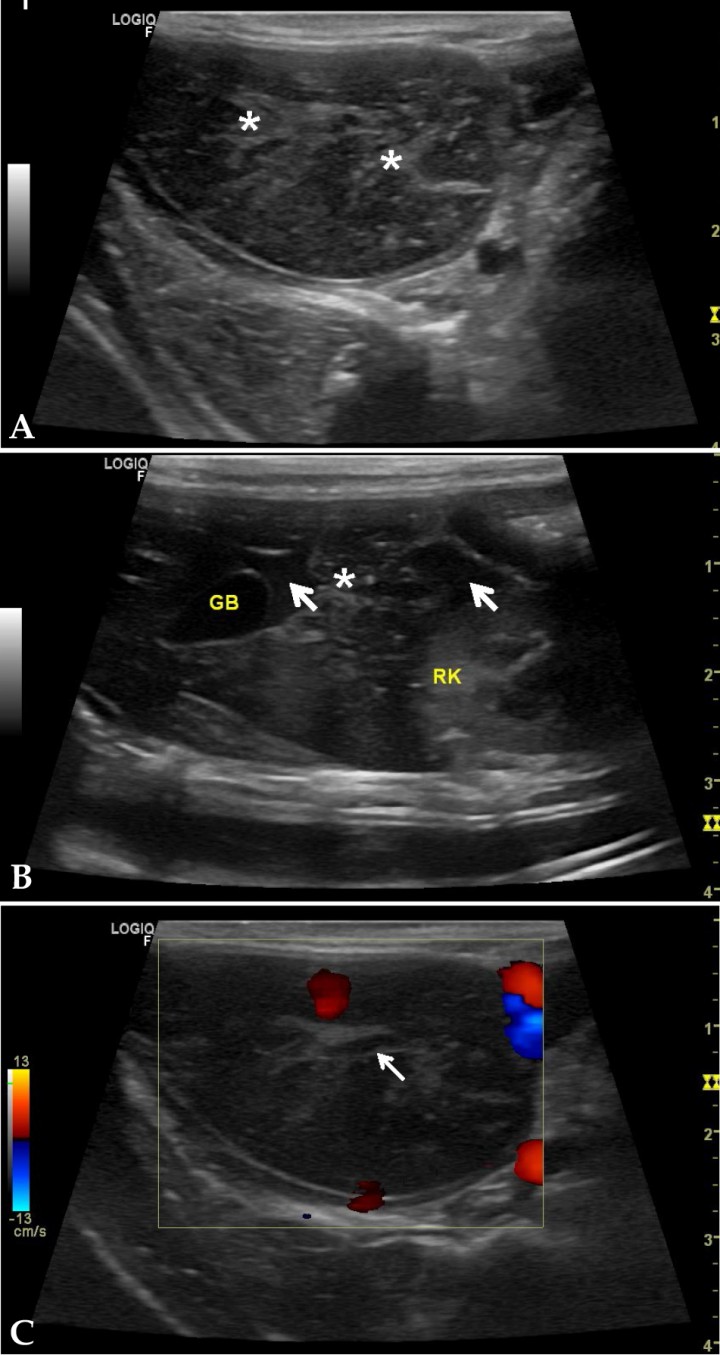

Ante la sospecha de una enfermedad hepática, las pruebas de diagnóstico por imagen, tales como la ecografía, son fundamentales para poder valorar la morfología e integridad del parénquima hepático y de las vías biliares. Se realizó una ecografía abdominal utilizando un transductor lineal de 6-12 MHz (Figs. 2A y 2B), observándose un aumento de tamaño de uno de los lóbulos hepáticos en lado derecho, compatible con el lóbulo caudado, con bordes redondeados y parénquima heterogéneo. Se apreciaba la presencia de líquido anecoico interlobar y aumento de ecogenicidad de grasa mesentérica perihépatica. A través del Doppler color (Fig. 2C) se puso de manifiesto la ausencia del flujo sanguíneo hacia el lóbulo afectado. Con los resultados del estudio ecográfico se sospechó la presencia de un lóbulo hepático torsionado, llegando al diagnóstico presuntivo de torsión de lóbulo hepático (TLH) en este conejo.

<p>Imágenes ecográficas del hígado en cortes longitudinales y parasagitales derechos. (<strong>A</strong>) Lóbulo hepático de ecogenicidad mixta (asteriscos sobre focos hiperecoicos), bordes redondeados, grasa mesentérica hiperecogénica. (<strong>B</strong>) Corte sagital a la altura de riñón derecho, presencia de contenido anecoico entre lóbulos (flechas blancas), área hepática con contorno irregular y ecogenicidad mixta (asterisco). (<strong>C</strong>) Corte longitudinal a nivel del hilio hepático utilizando el Doppler color sobre lóbulo afectado. Nótese ausencia de flujo en vena de paredes ecogénicas, vaso porta (flecha blanca). GB: vesícula biliar; RK: riñón derecho.</p>

Imágenes ecográficas del hígado en cortes longitudinales y parasagitales derechos. (A) Lóbulo hepático de ecogenicidad mixta (asteriscos sobre focos hiperecoicos), bordes redondeados, grasa mesentérica hiperecogénica. (B) Corte sagital a la altura de riñón derecho, presencia de contenido anecoico entre lóbulos (flechas blancas), área hepática con contorno irregular y ecogenicidad mixta (asterisco). (C) Corte longitudinal a nivel del hilio hepático utilizando el Doppler color sobre lóbulo afectado. Nótese ausencia de flujo en vena de paredes ecogénicas, vaso porta (flecha blanca). GB: vesícula biliar; RK: riñón derecho.

Las imágenes ecográficas pueden mostrar un aumento de tamaño del hígado, con bordes redondeados, el parénquima hepático puede ser hipoecoico o de ecogenicidad mixta, siendo la grasa y el mesenterio de alrededor hiperecogénico, y puede apreciarse, también, la presencia de líquido libre anecoico. El empleo del Doppler color y pulsado confirma la disminución o ausencia de flujo sanguíneo hacia el lóbulo afectado.[ Graham JE, Orcutt JC, Casale SA, et al. Liver lobe torsion in rabbits: 16 Cases (2007 to 2012). J Exot Pet Med 2014; 23:258-265. , Graham JE, Basseches J. Liver lobe torsion in pet rabbits: Clinical consequences, diagnosis, and treatment. Vet Clin North Am Exot Anim Pract 2014; 17:195-202. [PubMed] , Wenger S, Barrett EL, Pearson GR, et al. Liver lobe torsion in three adult rabbits. J Small Anim Pract 2009; 50:301-305. [PubMed] , Vilalta L, Espada Y, Majó N, Martorell J. Liver Lobe Torsion in a Domestic Ferret (Mustela putorius furo). J Exot Pet Med 2016; 25(4): 321- 326. , Pignon C, Donnelly TM, Mayer J. Hepatic lobe torsion in a rabbit (Oryctolagus cuniculus). Prat Méd Chirur l’Anim Comp 2013; 48(3): 91-98. ]